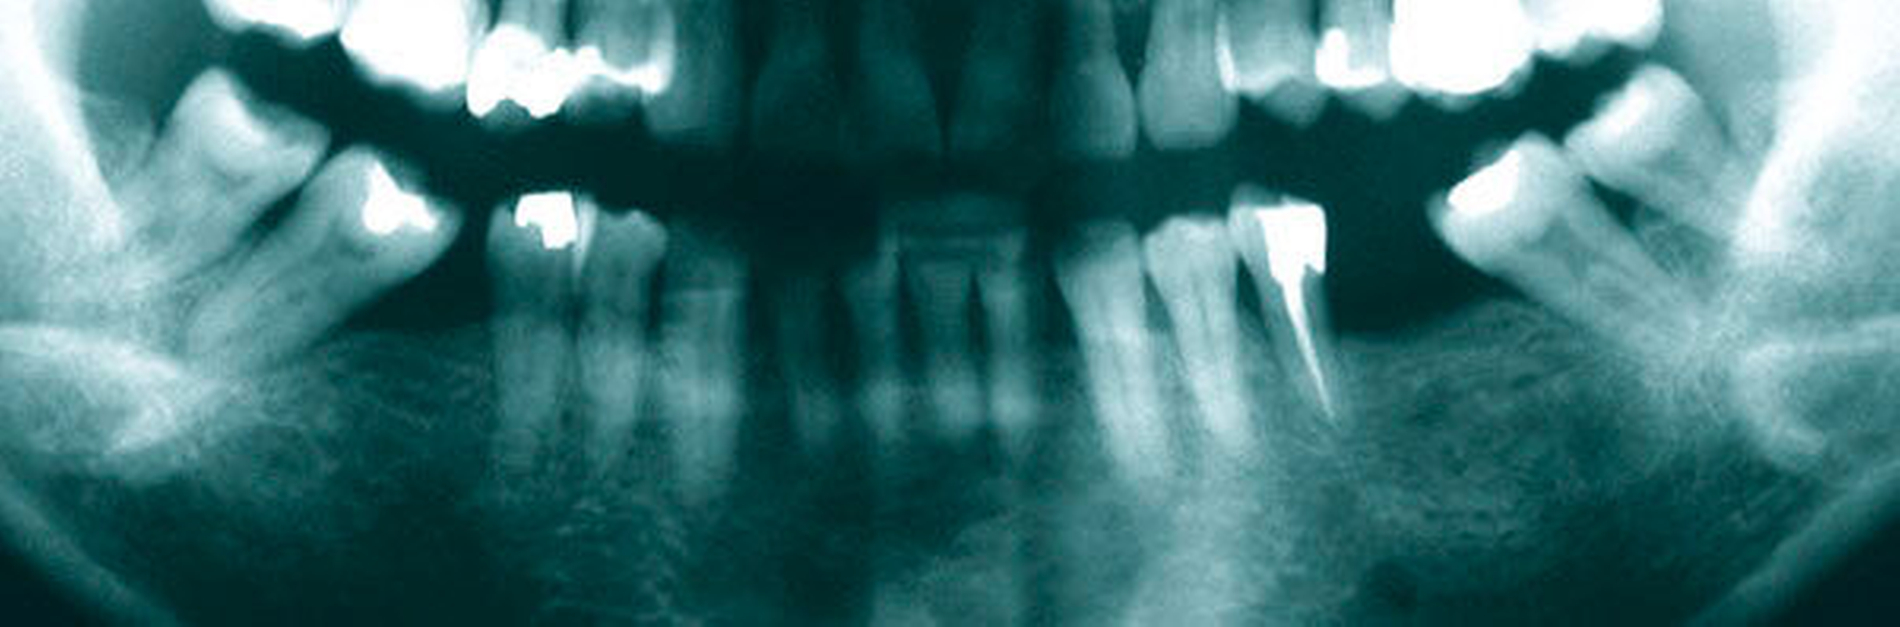

Abbildung 4: Überwachtes Monitoring (Belassen und Beobachten) von Zahnlücken

In der Zahnmedizin ist ein Dogma weit verbreitet: „Jede Lücke muss rasch geschlossen werden.“ Tatsächlich gibt es jedoch viele Situationen, in denen es ohne relevante funktionelle und ästhetische Einbußen vertretbar erscheint, eine Lücke zu belassen und regelmäßig zu beobachten (Monitoring). Derzeit erfolgt die Entscheidung „Lücke belassen versus Lücke schließen“ oftmals subjektiv. Sie ist zuweilen weniger von den Patientenvariablen abhängig als von den Schwerpunkten der betreuenden Zahnärzte (Abbildung 4) [Listl et al., 2016]. Ein fachlich fundiertes Vorgehen, das eine Entscheidung unter einer Nutzen-Risiko-Abwägung trifft und ein Monitoring in die Überlegungen einbezieht, kann ebenfalls in die Kategorie der frugalen Interventionen eingeordnet werden. Gleiches gilt für ein Vorgehen im Sinne des Prinzips der verkürzten Zahnreihe, das inzwischen wissenschaftlich gut evaluiert ist [Walter, 2016] und zu dessen Realisierung auch konservierende Maßnahmen beitragen können (Abbildung 5).

Falls ein Lückenschluss nach Gegenüberstellung der Vor- und Nachteile als angemessen angesehen wird, stellt sich die Frage, mit welchen Hilfsmitteln dies erfolgen soll. Derzeit stehen Implantate und klassische Brückenversorgungen im Vordergrund. Es gibt aber auch etliche nicht- oder minimal-invasive Alternativen, die zum Beispiel bei Einzelzahnlücken in Erwägung gezogen werden können. Dazu zählen unter anderem direkte Verfahren wie Zahnverbreiterungen oder -anhänger (Abbildungen 6 und 7) [Staehle, 2009 und 2012; Staehle et al., 2015]. Zurzeit kommen derartige Maßnahmen nur in Einzelfällen in Betracht, es bedarf noch weiterer Evaluationen, um ihr Indikationsspektrum genauer abgrenzen zu können. Es zeichnet sich aber jetzt schon ab, dass sie ein gewisses Potenzial als frugale Interventionen besitzen. Auch wenn momentan vielfach Implantate favorisiert werden, erscheint es dennoch sinnvoll, wenn die Zahnärzteschaft auch diverse Implantat-Alternativen vorhalten kann. Ungeklärte Probleme periimplantärer Entzündungen [Chrcanovic et al., 2016] und die zu erwartende Diskussion über Beziehungen zwischen periimplantären Entzündungen und der Allgemeingesundheit lassen es als sinnvoll erscheinen, solchen Fragen intensiver als bisher nachzugehen. Bislang wird zwar nur über Einflüsse der Allgemeingesundheit auf den Erfolg beziehungsweise Misserfolg von Implantaten diskutiert. Es ist aber nicht auszuschließen, dass man künftig die Fragestellung in umgekehrter Richtung dahingehend erweitert, inwieweit Implantate ihrerseits nicht nur positiven, sondern auch negativen Einfluss auf die Allgemeingesundheit nehmen können.